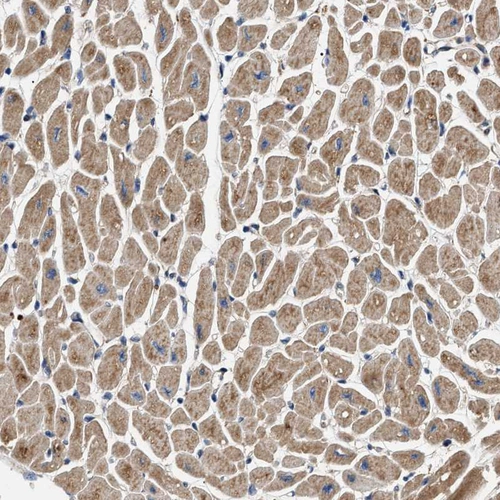

Immunohistochemical staining of human heart muscle, kidney, liver and testis using Anti-OXSM antibody HPA021300 (A) shows similar protein distribution across tissues to independent antibody HPA021293 (B).